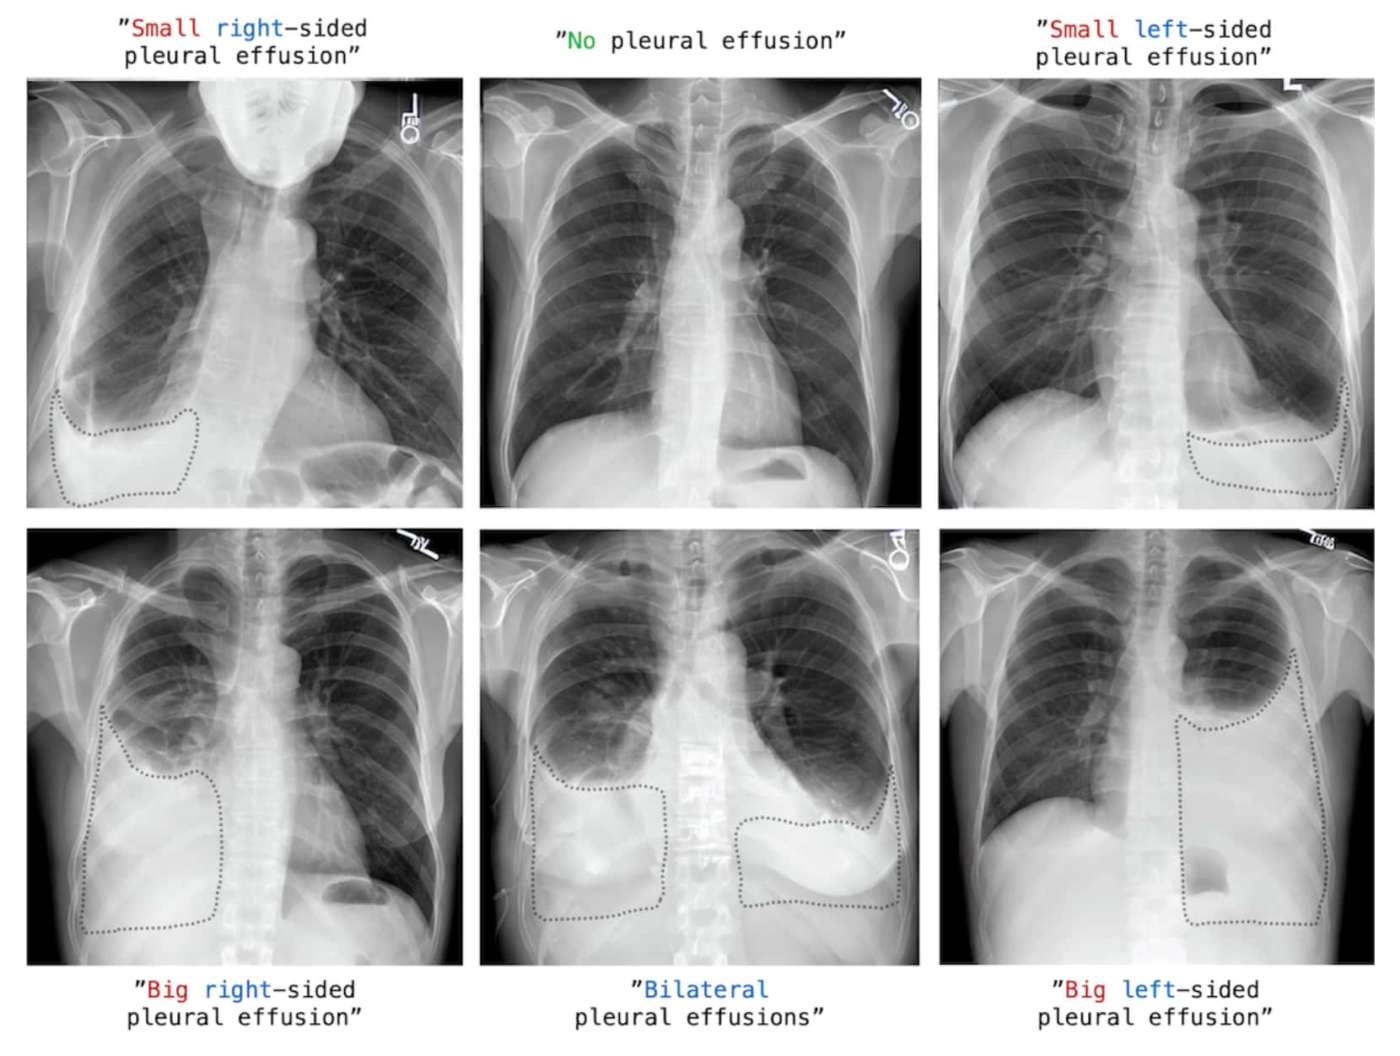

Tutto parte dal famosissimo modello AI aperto chiamato Stable Diffusion, quello che genera immagini a partire da un testo, il prompt: proprio come DALL·E 2 di OpenAI. Questi ricercatori hanno fatto un’operazione comune nel mondo dell’intelligenza artificiale chiamata fine tuning.

Stable Diffusion è capace di generare moltissime immagini, alcune meno bene di altre a seconda di quanti esempi di una certa immagine ha analizzato durante la sua fase di training.

Per insegnare a Stable Diffusion come generare immagini di cui ha poca o nessuna esperienza, è stato necessario eseguire l’operazione di fine tuning e mostrare a Stable Diffusion un certo numero di immagini di esempio.

I ricercatori della nostra storia hanno mostrato a Stable Diffusion quasi 350.000 immagini di radiografie del torace, accompagnate dal relativo rapporto del radiologo di turno.

A questo punto Stable Diffusion ha imparato a generare radiografie sintetiche, radiografie che non esistono nel mondo reale per dei casi rarissimi, a partire da una semplice descrizione dello scenario, il nostro prompt.

In questa maniera gli studenti possono esercitare le loro capacità di analisi e in situazioni che potrebbero incontrare solo una volta nella loro carriera e fare la differenza nel salvare vite umane.

Il progetto è bellissimo e molto promettente.